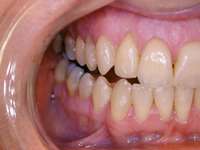

During the dental examination, dentists should look for excessive wear facets, which are likely to be a combination of parafunction and oral acidity. Obvious enamel defects from acid, including dentinal pooling (Figure 10), should be noted. Often the first signs of gastroesophageal reflux disease (GERD) are odontogenic, and there is a relationship between GERD and sleep apnea, with a proposed pathophysiology related to alterations in thoracic and abdominal pressure gradients.28,29 Positive responses should lead to referral to the sleep specialist. While the polysomnogram is indeed the gold standard in sleep medicine’s diagnostic regimen, various home-testing units are available (Figure 11).Many of these testing devices provide valuable information, yet they have some deficiencies as well.21,30 Most of them, at this point in time, do not evaluate EEG patterns and consequently do not detect alterations in sleep architecture. The lack of supervision with these home-testing units remains a concern; thus, at this time, these testing procedures generally are considered excellent screening devices but are not considered diagnostic by themselves and are generally not reimbursable by third-party payers in the United States. It is this author’s opinion, as well as the position of the American Academy of Dental Sleep Medicine, that while it may be, in some instances, in the patient’s best interest to have this ambulatory screening study completed, it is the responsibility of the dentist to then refer the patient to a sleep specialist for diagnostic purposes.31 It is essential to understand that there are non-obstructive sleep disorders that can be contributing to a patient’s signs and symptoms. Making a referral with information gained from the history and/or screening testing is an excellent service dentists can provide their patients.

Figure 10 Dentinal pooling and incisal scooping may be among the first signs of GERD, which can be a precursor to Barrett’s Syndrome.